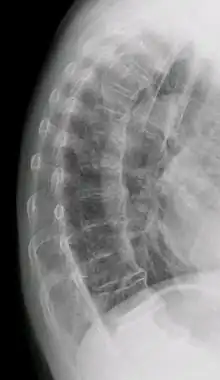

Ectopic calcification and new bone formation in diffuse idiopathic skeletal hyperostosis (DISH)